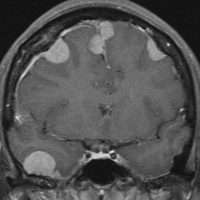

全髄膜の腫瘍化,NF-2

テント下を含めて頭蓋内の全ての髄膜が同時に腫瘍化してきます。この患者さんはNF-2なのですが,NF-2がない患者さんにもmeningiomatosisはあります。脳圧亢進による視神経乳頭萎縮で両側の視力が無くなるというような症状が出ます。これは手術適応がないタイプです。